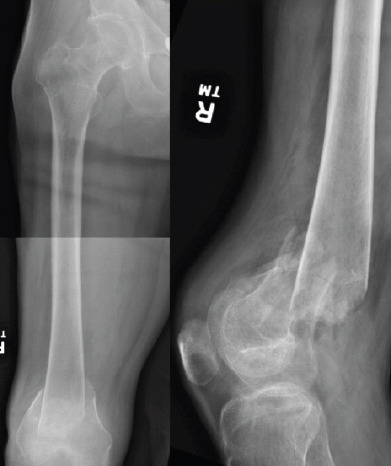

Case report: A 45-year-old male with T2 paraplegia presented with bilateral distal femoral shaft fractures following a motor vehicle accident. He underwent bilateral retrograde intramedullary nailing to preserve mobility and independence. Postoperatively, the patient developed a hypertrophic non-union on the right side with hardware migration, requiring revision with plate and screw fixation. Subsequently, he developed painful hardware on the right and severe heterotopic ossification on the left, significantly impacting his quality of life. Although hardware removal was recommended, the surgeries were never performed due to the patient's clinical course and eventual death from unrelated causes.